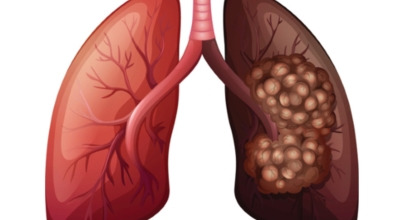

최근 슈퍼푸드로 주목받고 있는 적양파는 알리신 성분이 풍부한데요, 이 성분은 항염, 항균, 항산화 효과가 뛰어나 폐 건강에 좋은 채소입니다. 양파에 들어있는 퀘르세틴 성분도 항산화 작용을 하며 세포 손상을 예방해 폐에 생길 수 있는 염증이나 폐암을 미리 막아줍니다.

케일은 여러 매체에서 체중 감량에 효과적인 음식으로 잘 알려져 있죠. 페놀과 플라보노이드라는 성분이 폐암 예방에 큰 도움이 됩니다. 다른 채소들에 비해 유해 물질을 미리 차단하는 역할이 뛰어나 흡연자가 있다면 케일을 갈아 자주 마시는 것이 좋습니다. 쓴맛이 강해 케일만 갈아 먹기 힘들다면 사과 같은 맑은 즙이 나는 과일과 함께 갈아 드시면 훨씬 마시기 편합니다.

비트에는 매우 풍부한 항산화 성분이 함유되어 있습니다. 마그네슘, 칼륨, 비타민 C, 카로티노이드 같은 산화 억제 성분들은 폐의 염증을 완화하는 데 효과적이며, 천식, 기침, 폐렴 예방에도 도움을 줍니다. 특히 비트에 풍부하게 들어 있는 ‘베타인’이라는 성분은 암세포를 사멸시키는 역할을 하는데요, 한 연구에 따르면 베타인을 많이 섭취한 그룹의 폐암 발병률이 30% 이상 낮아지는 것으로 나타났습니다.